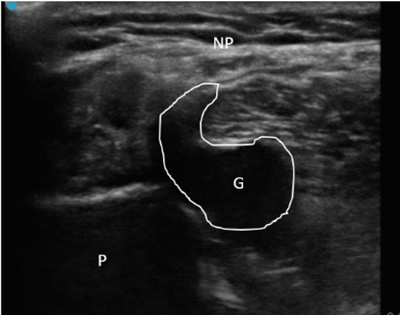

Se diagnosticó, por lo tanto, paresia de nervio peroneo derecho secundario a compresión por ganglión de articulación tibio-peronea proximal y se propuso al paciente un manejo intervencionista del mismo, que aceptó. Se realizó drenaje ecoguiado empleando una sonda lineal de alta frecuencia (10-5 MHz), una aguja de 20 G y una jeringa roscada de 5 ml (Figura 2), retirándose sin dificultad 1,5-2 ml de contenido mucinoso compatible con ganglión. Posteriormente se realizó infiltración de 1 ml de triamcinolona 40 mg ml diluida en 0,5 ml de mepivacaína al 2 %. Tras el procedimiento se evidencia una clara disminución del tamaño del ganglión.

Fig. 2. Ecografía en corte longitudinal de aspiración con aguja ecoguiada del ganglión. G: ganglión. A: aguja en interior de ganglión iniciando aspirado.